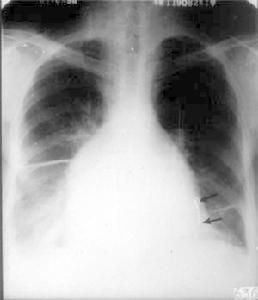

超聲心動圖在臨床上須與縮窄性心包炎鑑別,尤其右心室病變為主的限制型心肌病,二者臨床表現相似。在急性心包炎史、x線示心包鈣化,胸部ct或磁共振檢查示心包增厚,支持心包炎;心電圖上心房或心室肥大、束支傳導阻滯,收縮時間間期不正常支持心肌病,超聲心動圖對二者的鑑別有較大幫助,心尖部心腔閉塞及心內膜增厚確立心肌病的診斷。對於困難病例可作心室造影和心內膜心肌活檢。

X線表現3、超聲心動圖可見心內膜增厚,心尖部心室腔閉塞,心肌心內膜結構超聲回聲密度異常,室壁運動減弱。在原發性患者室壁不增厚,在浸潤性病變室壁可以增厚,舒張早期充盈快,中、後期則極慢。心包膜一般不增厚。